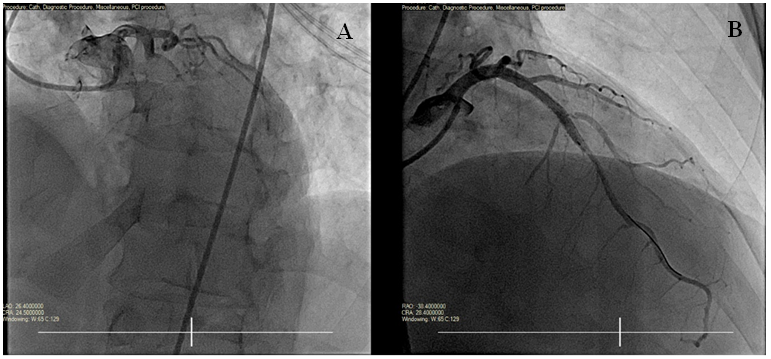

The initial troponin value was mildly elevated. The patient was given therapeutic lovenox and ticagrelor. He was taken emergently to the cardiac catheterization laboratory. The cardiac angiogram demonstrated proximal LAD occlusion (Figure 2) and no significant disease of any other coronary artery. Percutaneous coronary intervention (PCI) of the proximal LAD with drug-eluting stent (DES) was performed (Figure 2). After PCI, the patient reported resolution of his symptoms. His post-revascularization ECG showed resolution of the acute ST changes. He was started on dual antiplatelet therapy. A post-revascularization echocardiogram showed focal wall motion abnormalities and a preserved ejection fraction of fifty percent. Guideline-directed medical therapy was started.

Figure 2 Cardiac catheterization. A: Proximal LAD occlusion. B: Revascularization after stent deployment to the LAD.

This patient was found to have an acutely occluded proximal LAD when taken for emergent cardiac catheterization (Figure 2). The ECG demonstrates de Winter syndrome, a finding specific to proximal LAD occlusion. This syndrome is characterized by upsloping 1-3 millimeter ST-segment depression at the J point in leads V1-V6 which progresses into tall, symmetric T waves in these leads.1 One-to-two millimeter ST-segment elevation in lead aVR can also be seen and was present in this case. Though hyper acute T waves can be present in hyperkalemia, this electrolyte abnormality is also associated with widened QRS complexes. De Winter syndrome is distinguished from hyperkalemia by the presence of the characteristic upsloping ST-segment depressions and absence of widened QRS complexes.